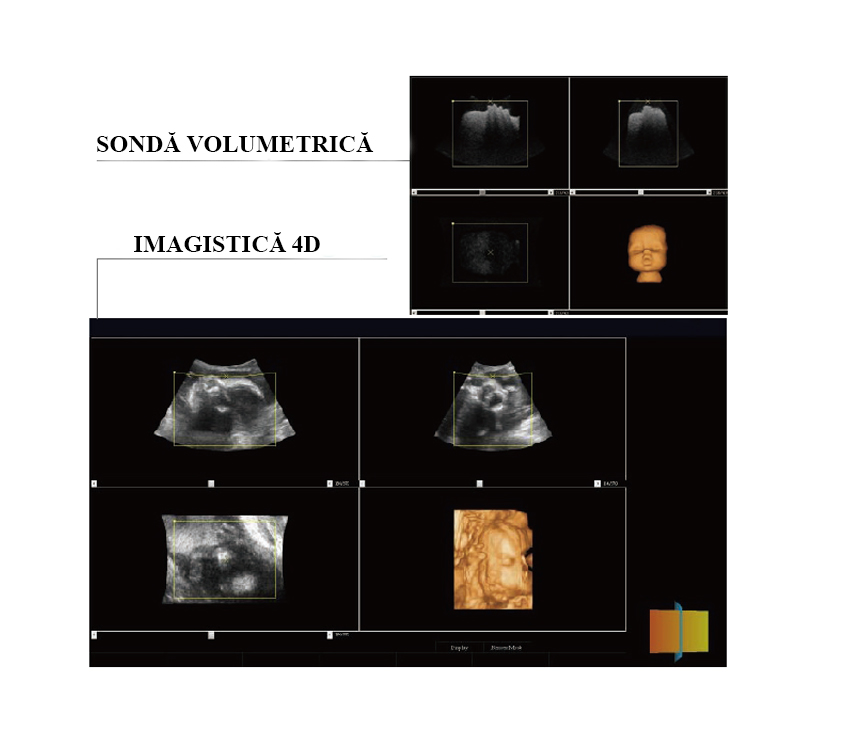

Modelul este echipat cu tehnologie avansată 4D D-Live, destinată obținerii imaginilor volumetrice în timp real, cu randare realistă a structurilor anatomice și optimizare a percepției profunzimii.

OB&GYN – Tehnologie avansată 4D D-Live

Imagistica 4D (3D în timp real) oferă vizualizare volumetrică dinamică a structurilor anatomice, permițând evaluarea interactivă și detaliată în aplicațiile obstetricale și ginecologice.

Examinările 4D sunt realizate cu ajutorul unei sonde volumetrice dedicate, echipată cu mecanism intern de scanare automată prin oscilație controlată. Această tehnologie permite achiziția continuă și stabilă a volumelor, generând imagini uniforme, cu reducerea artefactelor de mișcare și creșterea reproductibilității examinării.

Tehnologia D-Live integrează o sursă de iluminare virtuală reglabilă, care optimizează redarea volumetrică prin simularea efectului de lumină și umbră. Rezultatul este o vizualizare realistă, cu percepție îmbunătățită a profunzimii și evidențiere clară a detaliilor anatomice.

Reconstrucție RealSkin

Funcția RealSkin utilizează algoritmi avansați de procesare spațială tridimensională pentru a genera imagini 4D cu randare stereo-realistă, depășind limitările ecografiei convenționale în mod grayscale.

Comparativ cu imagistica 4D standard, tehnologia RealSkin oferă:

- câmp de vizualizare extins,

- contrast îmbunătățit,

- claritate superioară a contururilor,

- evaluare morfologică optimizată.